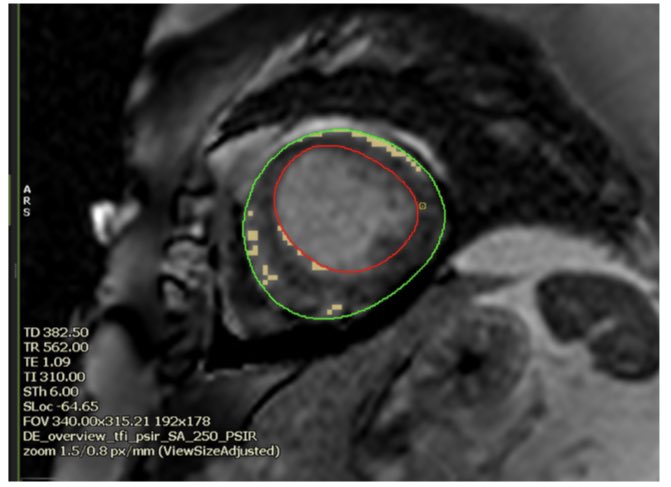

#whyCMR LGE at +3SD threshold, none at +5 SD threshold @circlecvi @drkartikganga @avinash230791 @Ahmed43101178 , raised T1 and T2 mapping values

#whyCMR in TC: absence of LGE (at +5SD threshold) , but recent studies suggest LGE may be present

absence of LGE (at +5SD threshold) , but recent studies suggest LGE may be present